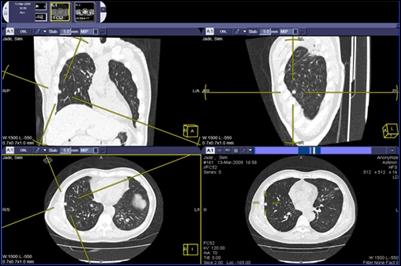

August 3, 2011 - The latest release of McKesson's radiology information system (RIS) and picture archiving and communication system (PACS) have both infrastructure updates and usability enhancements. These systems offer value for medical imaging workflows, from order entry to data storage, image analysis and report distribution. The company said these solutions have a complete end-to-end workflow in one workspace and offer clinical, financial and operational benefits that address healthcare IT challenges both today and for the future.

A radiologist productivity tool acts as a natural extension to display protocols for efficient analysis of complex, high-volume studies. Newly released Report Connector software addresses the needs of multi-vendor, heterogeneous environments.